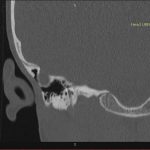

- Diagnosticul traumatismelor de bază de craniu

- Diagnosticul fracturilor:

- Complexe cranio-sinusale

- Complexe cranio-etmoidale

- Complexe cranio-orbitare

- Complexe cranio-faciale